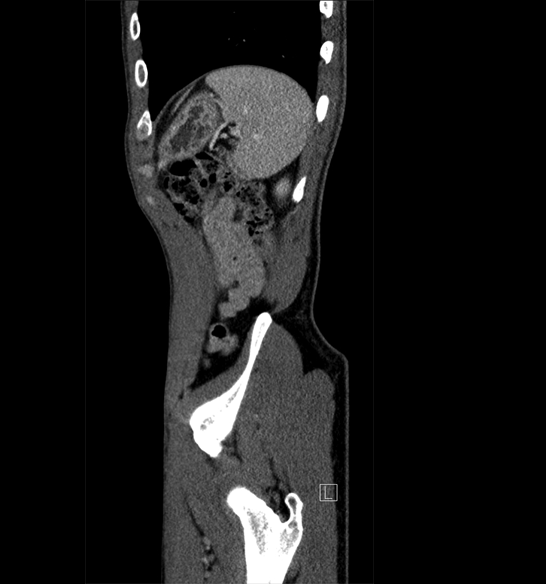

Body

Covers abdominal CT anatomy.